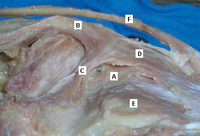

Anatomical dissection of the posteromedial knee capsule. The weak area (A) is identified between the two expansions of the semimembranosus muscle (B), the oblique popliteal ligament (C), and the expansion over the sheath of the popliteus muscle (D). The semitendinosus muscle (E) and popliteus muscle (F) are also indicated

Adapted from Labropoulos N, Shifrin DA, Paxinos O. New insights into the development of popliteal cysts. Br J Surg. 2004;91:1313-1318; used with permission

Popliteal cyst lying in its most common location in the posteromedial popliteal fossa (A), dissecting through the deep fascia (B) and the medial head of the gastrocnemius muscle (C)

Deep dissection of the posteromedial capsule. The two expansions of the semimembranosus muscle have been elevated, exposing the weak area of the capsule between the posterior cruciate ligament (A) and the posterior horn of the medial meniscus (B) that gives entry to the knee joint. The medial femoral condyle is also visible (C)